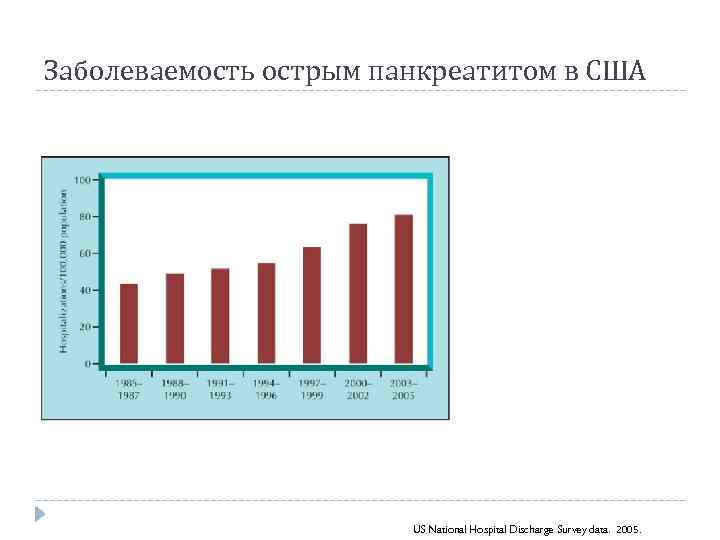

Заболеваемость острым панкреатитом в США US National Hospital Discharge Survey data. 2005.

Заболеваемость острым панкреатитом в США US National Hospital Discharge Survey data. 2005.